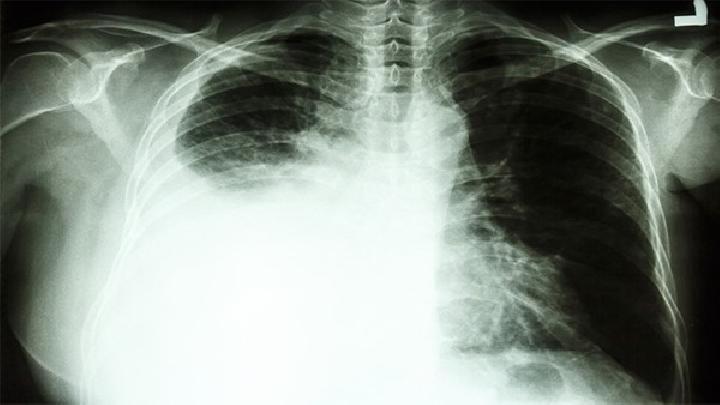

如何确诊肺结核呢?对于肺结核一定要确诊后才能找到治疗的方法,但是不少的人都因为没有及时的检查确诊导致了肺结核变得更加的严重,到底该怎么确诊呢?下面我们一起来了解下吧!

很多朋友对肺结核的检查方法不是很清楚,很多人认为了解这些没用,其实是错误的,如果我们掌握这些的话,就能够及早发现,及早的进行治疗,避免此病的危害降临在自己头上,那么检查肺结核的方法有哪些呢,以下是详细介绍。